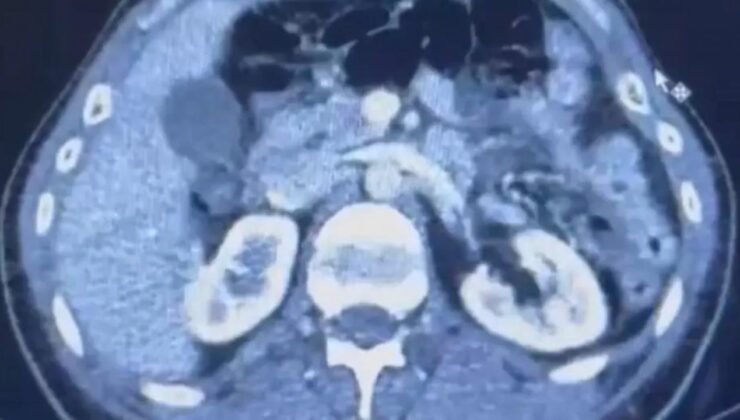

Kayseri’de gözaltına alınan İranlı şüphelilerin midelerinden uyuşturucu kapsülleri çıktı.İl Emniyet Müdürlüğü Narkotik Suçlarla Mücadele Şube Müdürlüğü ekipleri, uyuşturucu ticareti yapan kuryelerin yakalanmasına yönelik çalışma başlattı.İran uyruklu üç şüphelinin yurt dışından Türkiye’ye uyuşturucu getireceği bilgisi alındı.Şüphelilerin bulunduğu adreslere düzenlenen operasyonla S.C. (41), G.M. (28) ve R.B.C. (35) gözaltına alındı. RÖNTGEN ÇEKİLDİ, KAPSÜLLER ORTAYA ÇIKTIŞüphelilerden S.C. ve R.B.C. muayene edilmek üzere Kayseri Şehir Hastanesi’ne getirildi.Röntgeni ve ultrason çekilen şüphelilerin midesinde yaklaşık 50 kapsülde 554 gram uyuşturucu olduğu tespit edildi.Uyuşturucular sağlık ekiplerinin tedavisiyle çıkarıldı.Üç şüphelinin emniyetteki işlemleri ise sürüyor.KAYNAK: DHA